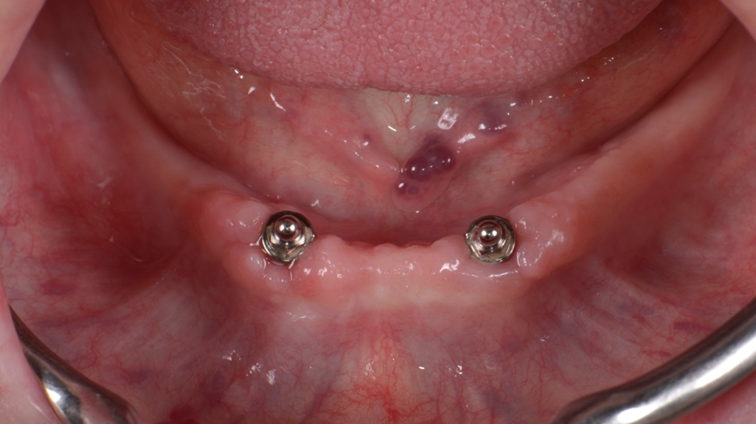

Dois meses após a cirurgia, instale os componentes o’ring nos implantes (Figura 9). E faça a captura das cápsulas na prótese provisória a fim de que o paciente já se acostume com a prótese total mucossuportada implantorretida (Figura 10).